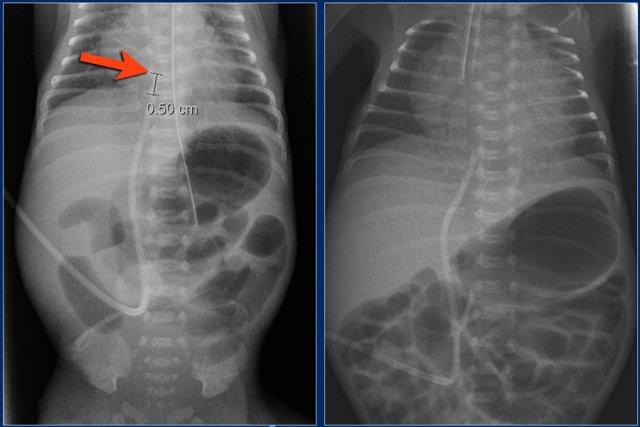

• The umbilical venous line is too deep and positioned in the right atrium.

• The umbilical arterial line is at the level of T10 (preferrably at level T6-T9).

• The endotracheal tube is positioned too deep.

It should be 1 cm above the trachea bifurcation.